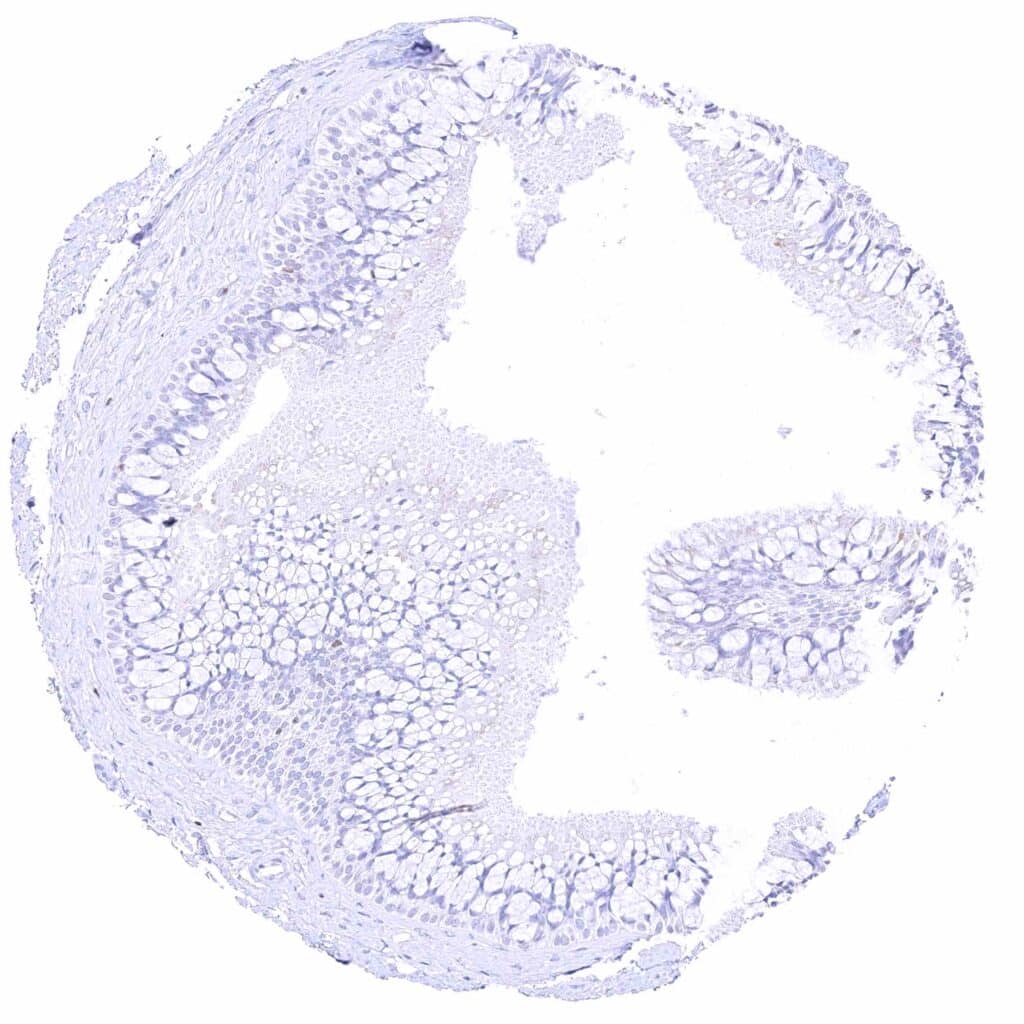

Uterus, ectocervix – Weak to moderate nuclear GATA3 staining of squamous epithelial cells.

Uterus, endocervix – Granular cytoplasmic GATA3 positivity of epithelial cells.

Skin – Strong nuclear GATA3 staining of squamous epithelial cells.

Skin, anal canal – Weak to moderate nuclear GATA3 staining of squamous epithelial cells. The staining predominates in the lower half of the epidermis.